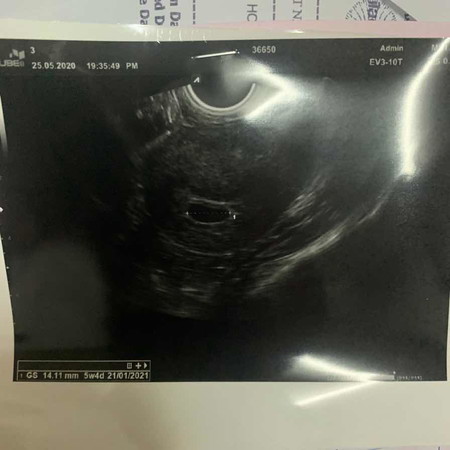

เมื่อวานไป us มา อายุครรภ์5 week4d ควรเจออะไรนอกจากถุงไหมค่ะ มีแม่ๆบ้านไหนที่ us อายุครรภ์แค่นี้แล้วเจอแค่ถุงบ้างค่ะ แม่กลัวจะเป็นท้องลมมากค่ะ

6 weekแล้วเจอแต่ถุง แต่ยังไม่เจอหัวใจเต้นกังวลเหมือนกัน กลัวท้องลมรอบสอง